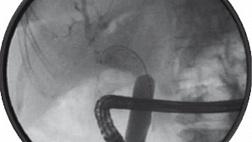

Через 6 часов у пациентки возникла массивная рвота кровью и тяжелый гиповолемический шок. Попытка проведения эзофагогастроскопии оказалась неудачной из-за большого количества крови и сгустков в пищеводе и желудке. Потребовалась лапаротомия, в ходе которой батарея была извлечена, но, несмотря на это, кровотечение продолжалось, состояние пациентки оставалось крайне тяжелым. С гемостатической целью девочке был установлен зонд Сенгстакена — Блэкмора. Но при повторном эндоскопическом исследовании выявлено, что источник кровотечения расположен в средней трети пищевода (рис. 2 — A).

Рисунок 2 [1].

Зонд был удален, установлен баллонный дилататор диаметром 20 мм (CRE PRO, Boston Scientific) — это позволило выполнить аортографию, которая показала экстравазацию контраста, подтверждая подозрение на повреждение аорты несколько выше диафрагмы (рис. 3).

Эндоскопическое исследование через год показало полную реэпителизацию на месте кровотечения из пищевода (рис. 2 — B). Наблюдение в течение трех лет не выявило каких-либо осложнений.